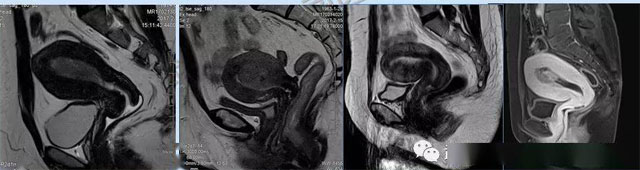

婦科疾病常常讓女性陷入了焦慮。主要是這類疾病婦女有難言之隱,癥狀隱匿,病情復(fù)雜。磁共振體檢車的金光火眼能力可以破解各種婦科難題。哪些情況需要使用磁共振檢查,檢查過程是否有不適。這些都是可以解決的。例如子宮常見疾病的磁共振診斷。

磁共振VS傳統(tǒng)檢查:有這些優(yōu)勢?無輻射安全系數(shù)高,磁共振沒有電離輻射,適合備孕跟孕婦檢查。它對軟組織有高清的成像效果,可以清晰的看到子宮各層的結(jié)構(gòu)??梢宰R別細(xì)小的肌瘤,早期的癌癥腫瘤。可以發(fā)現(xiàn)其他設(shè)備難以檢查到的深部子宮內(nèi)膜異位結(jié)節(jié)。多序列成像和增強掃描檢查,判斷腫瘤的良性準(zhǔn)確率高達(dá)90%以上。